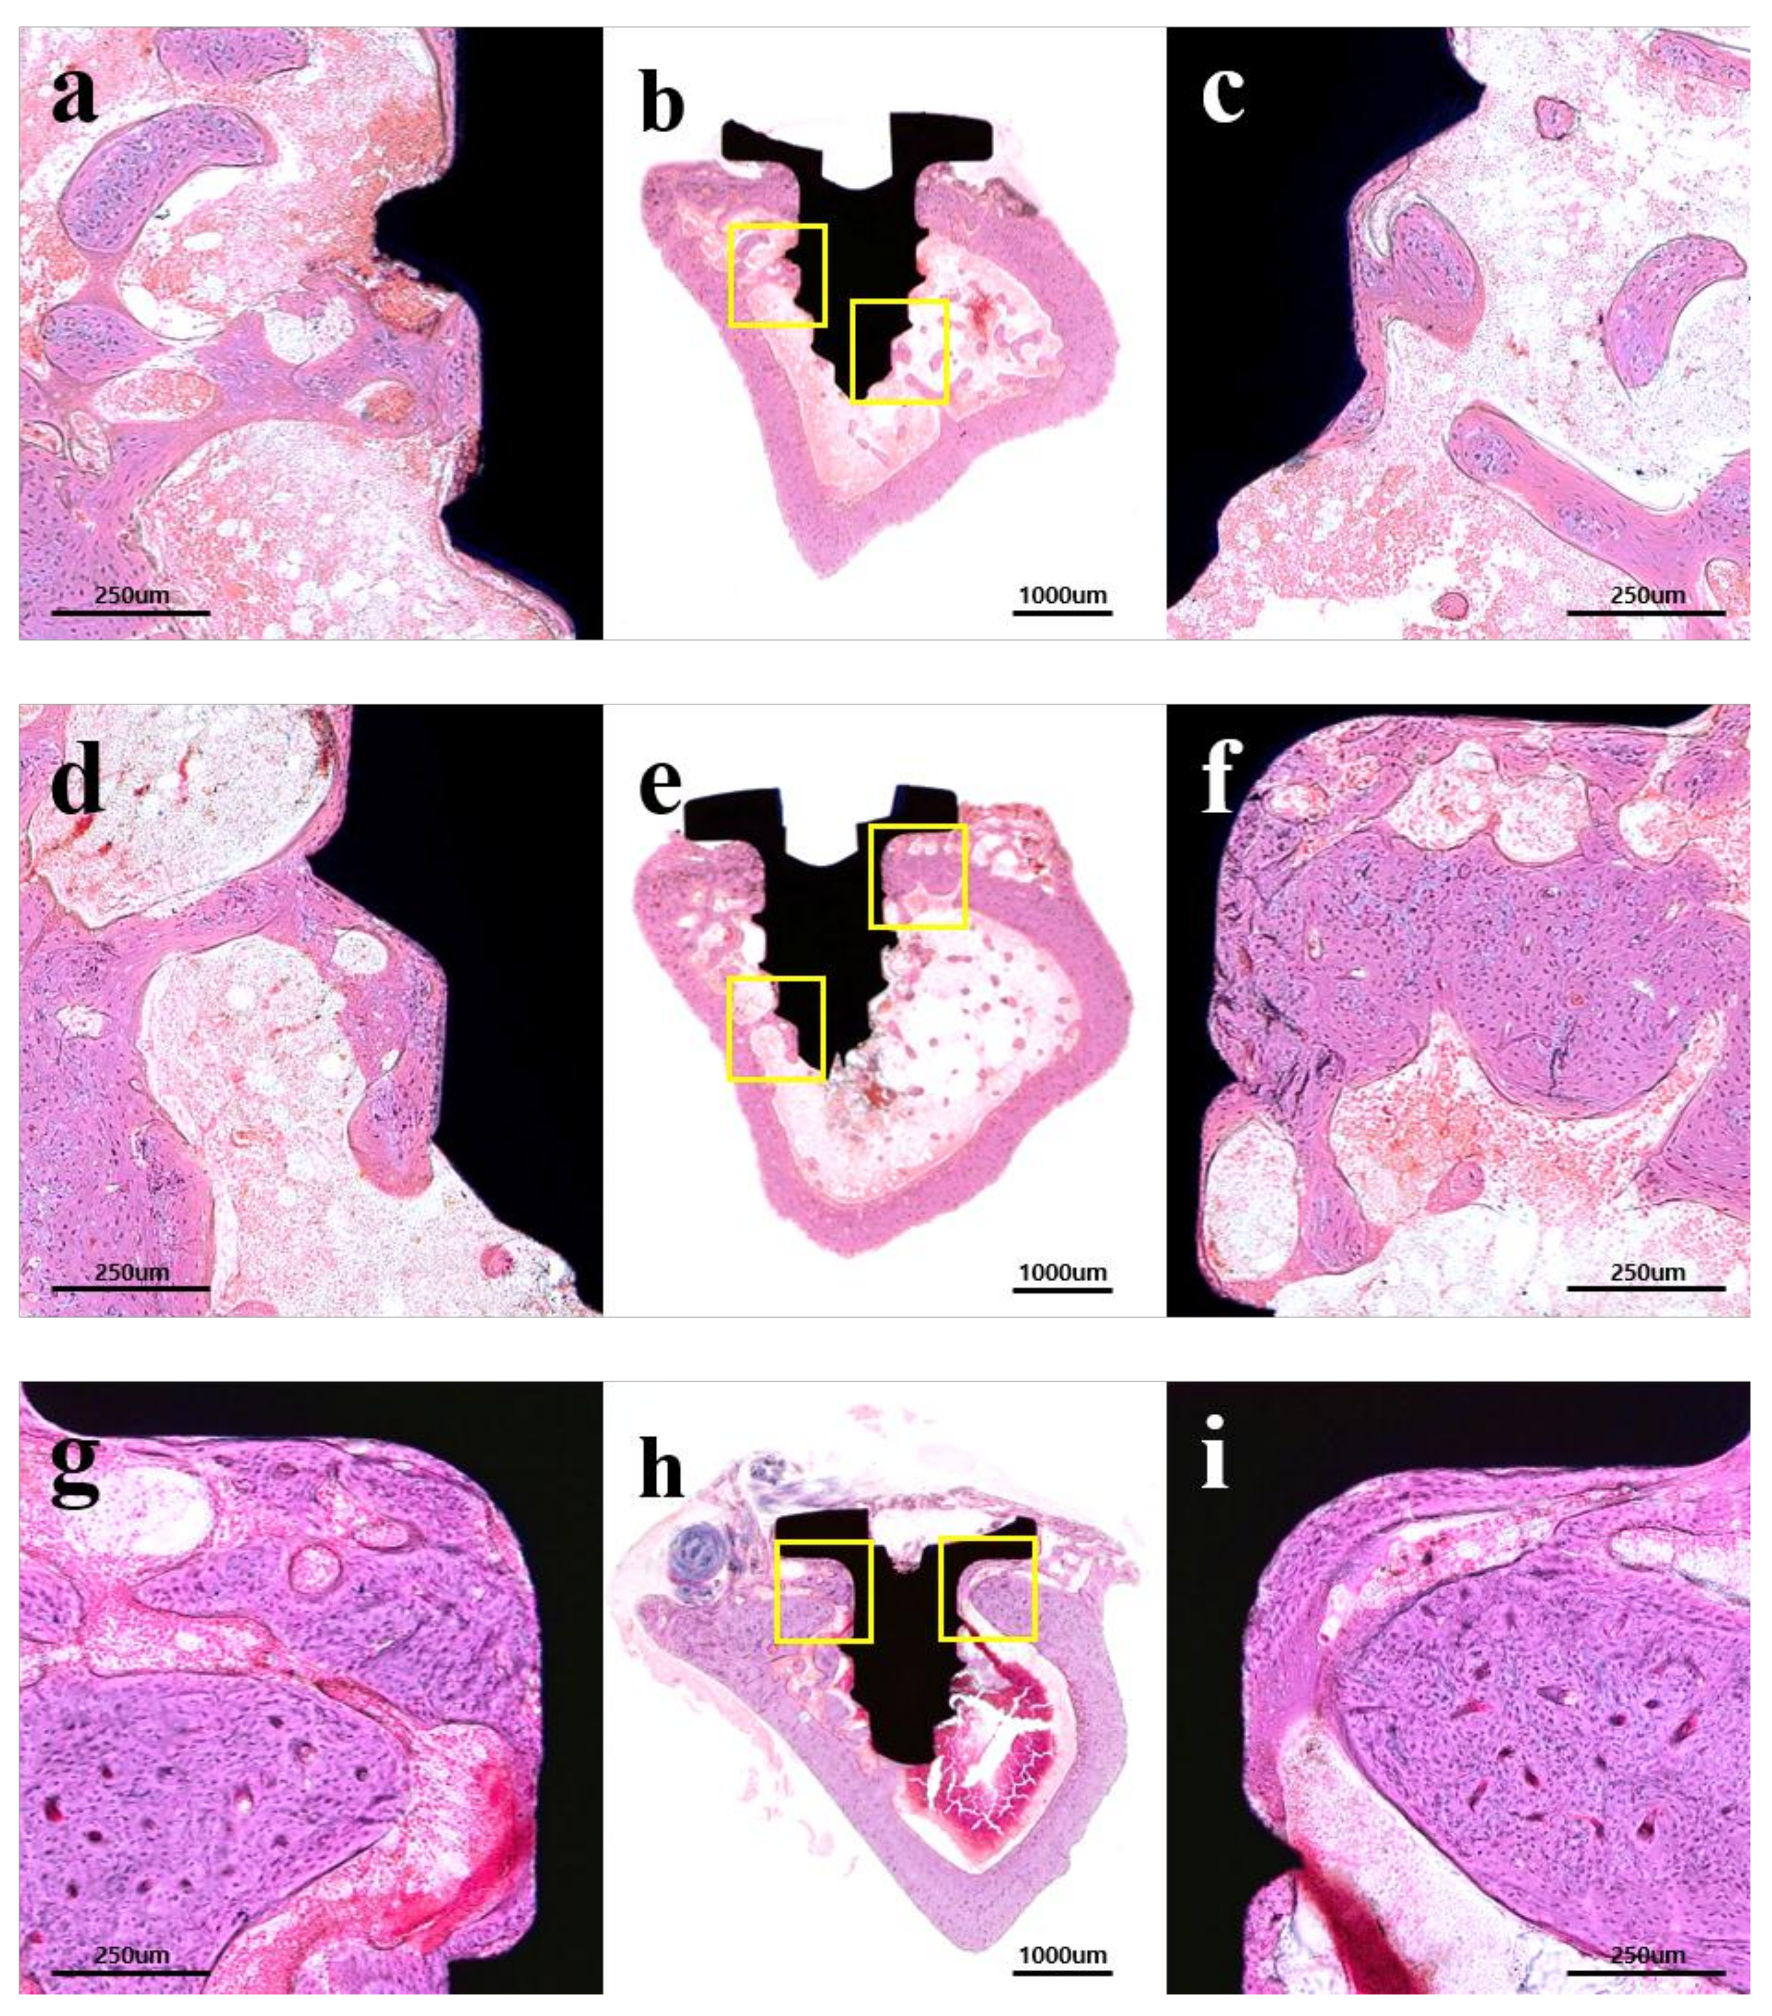

2.2.3. Histological Findings

2.2.4. Histometric Findings

4.3.4. Histology Analysis